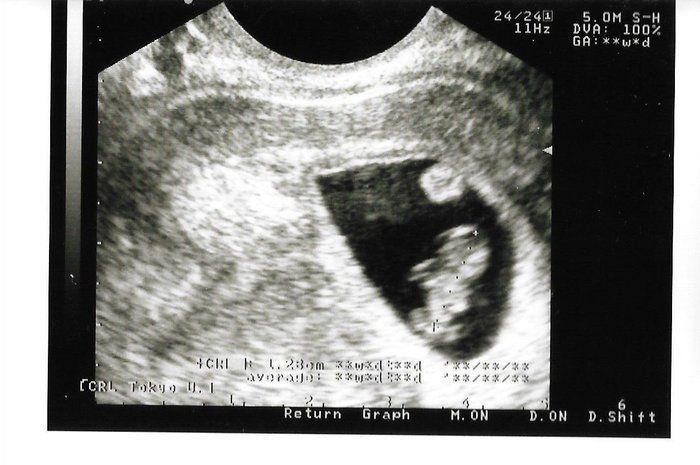

Chisatoさんの妊娠8週のエコー写真 手足が分かる。小さくてかわいい

さらに約10日後。赤ちゃんが少し人の形になってきていて、頭、手足がある様子が見てとれます。赤ちゃんの上部にある丸いものは、「卵黄嚢(らんおうのう)」だそうです。おなかの中がこんなに良く見えて、本当にびっくりでした。小さな心臓が元気に動いているのも確認できました。赤ちゃんの大きさは1.28cm。

私は、妊娠のかなり初期からつわりがあり、この頃は気分が悪くなるのが怖くて外食に行く勇気が出ませんでした。